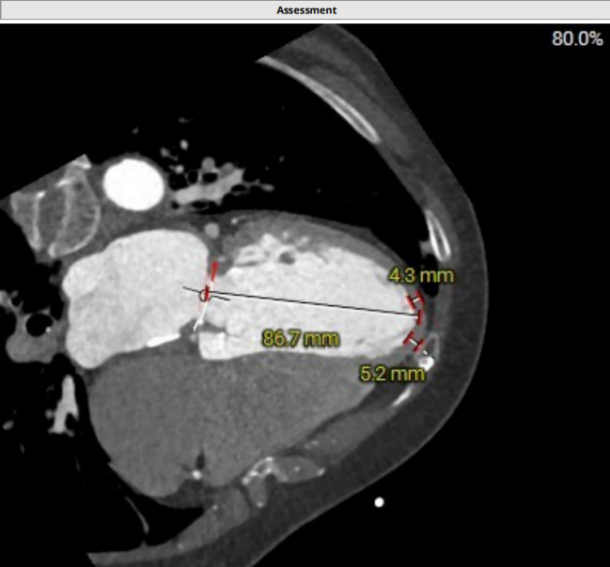

心尖投影位于第六肋间,心尖部心肌厚度4.3-5.2mm